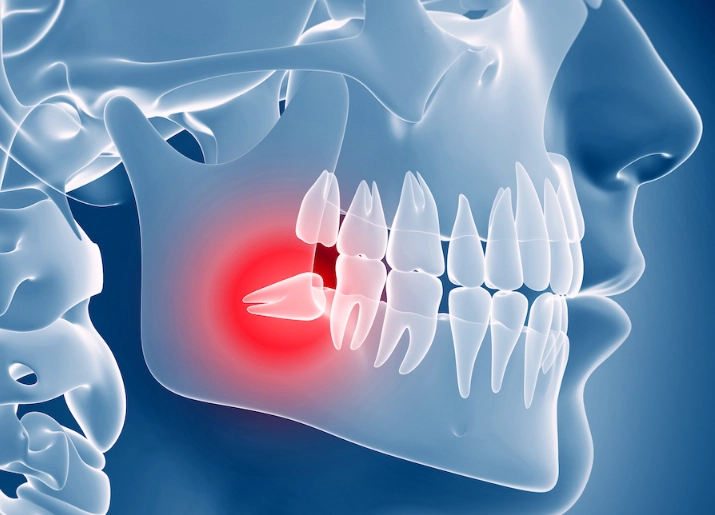

The Problem of Impaction

An impacted wisdom tooth is one that fails to fully emerge through the gums. It gets stuck. This is the core issue for most severe pain cases. The type of impaction dictates the kind of trouble you'll have.

It's not just "teeth coming in." The pain originates from a fundamental mismatch: our jaws have evolved to be smaller, but we still grow the same number of teeth. Your third molars, the wisdom teeth, are the last to erupt, usually between ages 17 and 25. By then, there's often no room left.

This space crunch leads to several specific, painful scenarios: